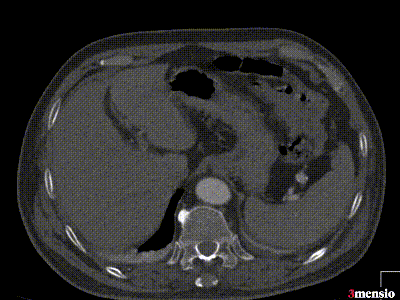

案例三(梯形瘤颈):3年前肾结石,在治疗复查过程中发现腹主动脉瘤。

案例四(梯形瘤颈):因下肢髋部疼痛行腰椎检查时发现腹主动脉瘤,进一步CTA认证确诊为腹主动脉瘤。

案例五:查体发现腹主动脉,行CTA确认腹主动脉瘤伴血栓形成。